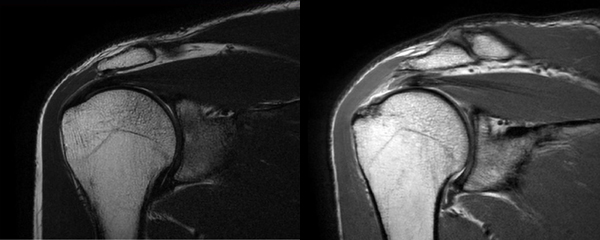

방사선학적 검사와 자기공명영상(MRI) 검사 결과 우측 견관절 회전근개의 전층 파열 소견이 관찰됐다. 관절내시경을 사용해 봉합술을 시행한 이후 충분한 재활기간을 거치면서 경과가 좋아 지금은 별다른 통증 없이 지낼 수 있게 됐다.

회전근개 파열을 파열 두께에 따라 부분 파열, 전층 파열로 구분하기도 하며 파열 범위에 따라 소파열, 중파열, 대파열, 광범위 파열로 구분하기도 한다. 부분 파열의 경우는 수술적 치료를 하기도 하지만 수술적 치료 없이 삼각근 강화 운동과 주사 치료, 약물 치료로 파열의 진행을 늦추고 통증을 감소시킬 수 있다.

파열 범위에 따라 소파열, 중파열 정도까지는 관절경적 봉합 수술을 시행하면 재파열이 되는 경우가 적고 수술 후 일상생활도 복귀도 빠르다. 하지만 파열 범위가 대파열 이상 진행하게 되면 관절경적 봉합술을 하더라도 재파열율이 증가하게 된다.

회전근개 힘줄 파열이 오래되고 진행하게 되면 힘줄에 연결돼 있는 근육은 일을 하지 못하게 돼 퇴화하게 되며 근육이 점차 지방 조직으로 변하게 되는데 이를 지방 변성(fatty degeneration)이라고 한다. 지방 변성돼 있는 회전근개 근육은 파열된 부위를 당겨서 제자리로 위치하지 않을 가능성이 높게 되며 관절 내시경을 사용해 봉합을 하더라도 완전 봉합을 못할 수 있다.